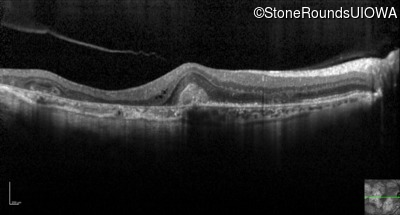

Optical Coherence Tomography - Right - 20/40 -2

Exemplar / OCT Stack

OCT Stack